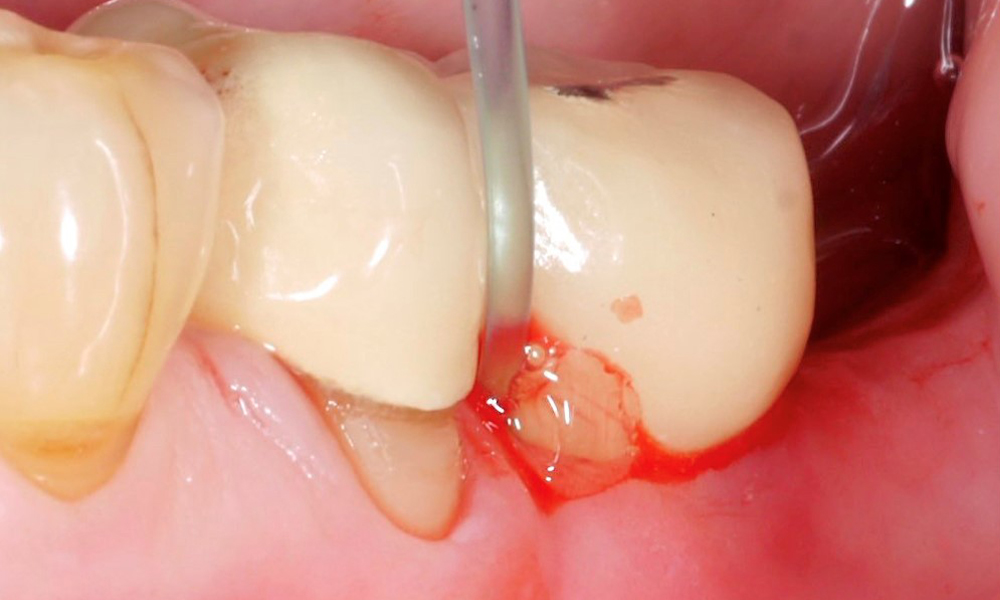

Die effiziente und erfolgreiche Reinigung der Implantatoberfläche ist wohl einer der kritischsten Faktoren bei der Behandlung von Periimplantitisfällen. In einem früheren Bericht ( „Nicht-chirurgische Periimplantitistherapie – Goldstandard ...?“) wurden die Ergebnisse des 18. Europäischen Workshops zur Parodontologie, der im Herbst 2022 stattfand, zum Thema mechanische Reinigung bei der Behandlung von Periimplantitisfällen diskutiert. Es besteht aber natürlich auch die Möglichkeit diese mechanische Reinigung der Implantatoberfläche durch eine zusätzliche chemische Reinigung zu unterstützen.

Die vorhandene Evidenz zur zusätzlichen chemischen Reinigung der Implantatoberfläche wurde von de Waal und Kollegen (2022) zusammengefasst. Doch leider kommen wir auch hier – ähnlich zur mechanischen Reinigung – zu der Schlussfolgerung, dass es für klare Behandlungsrichtlinien für periimplantäre Erkrankungen noch immer zu wenige, gut durchgeführte Studien gibt. So konnte diese Forschungsgruppe zum Thema „chemische Reinigung“ lediglich 3 Studien identifizieren und in der systematischen Übersichtsarbeit zusammenfassen.

In zwei Studien wurde der Effekt der anti-mikrobiellen photodynamischen Therapie untersucht und in einer Studie der Effekt eines Gels spezifisch zur Reinigung der Implantatoberfläche. In allen drei Studien wurden diese chemischen Methoden zusätzlich zur submukosalen, mechanischen Reinigung eingesetzt, die beispielsweise aus Ultraschall- und/oder Pulverstrahlbehandlung bestand. Alle drei Studien zeigten bessere Ergebnisse in Bezug auf die Reduktion der Sondierungstiefe, während alle anderen Parameter, wie Blutung auf Sondieren oder Behandlungserfolg, nicht eindeutig ausfiel.